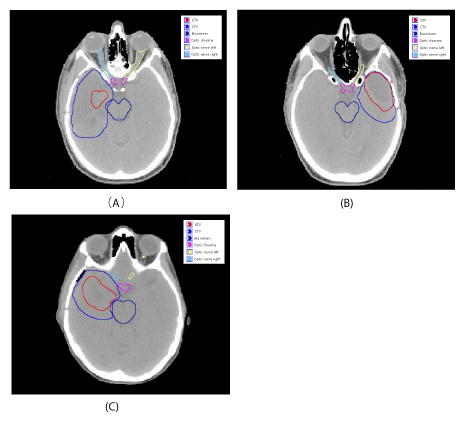

We selected three brain tumor patients, who were treated with proton therapy at the University of Texas MD Anderson Cancer Center. Figure 1 shows the target volumes, target locations and organs at risk in the brain tumor treatment plans on a computed tomography slice. The tumors are surrounded in a complicated manner by nerve, brain, brainstem, bone, and sinus cavity. The gross tumor volume (GTV) and the clinical target volume (CTV) for each case are 6.3 cc and 111.8 cc for case (A), 37.4 cc and 70.4 cc for case (B), and 27.1 cc and 84.4 cc for case (C).

Figure 1: Contours of the GTV, CTV, and OARs drawn on the computed tomography image for three brain cancer patients..